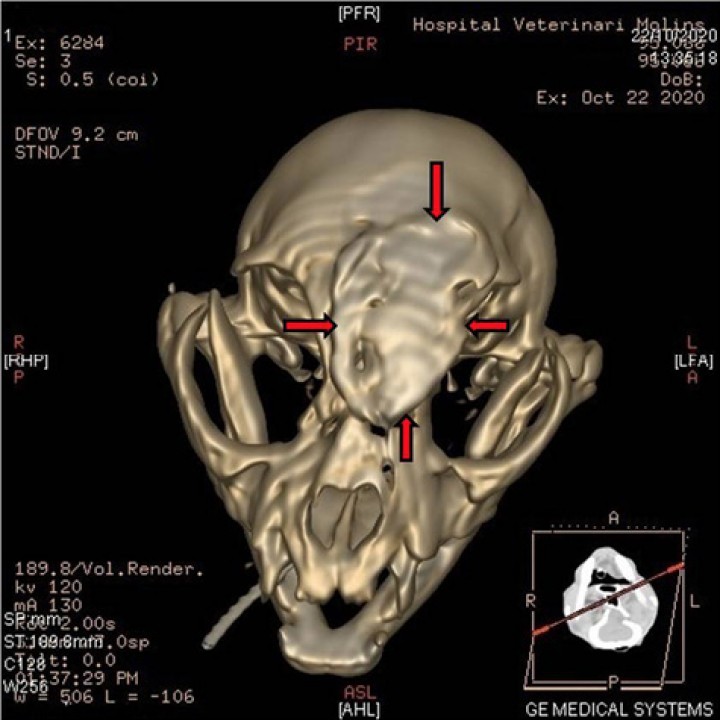

<p>Reformateo 3D, vista dorsal del cráneo que muestra las fracturas a nivel frontal que provocan el desplazamiento en dicha zona (flechas).</p>

Reformateo 3D, vista dorsal del cráneo que muestra las fracturas a nivel frontal que provocan el desplazamiento en dicha zona (flechas).

Se observaron fracturas en los huesos de las tres principales subdivisiones del cráneo: cara (maxilar, palatino), bóveda craneal (frontal y etmoides) y base de cráneo (preesfenoides). El estudio completo del TAC reveló fracturas conminutas y simples, la mayoría desplazadas y/o deprimidas (Fig. 4).